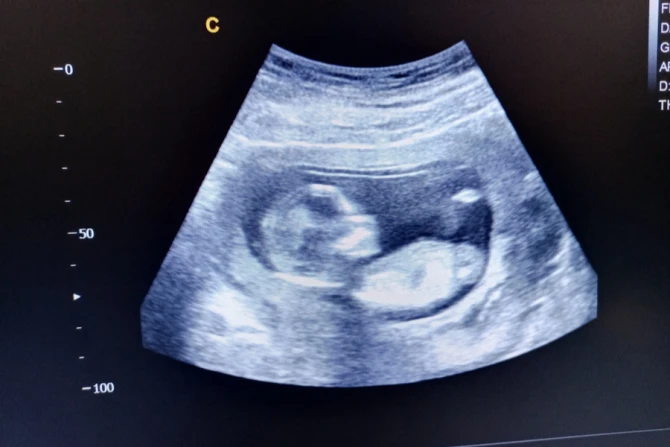

The survey of likely voters, conducted by OnMessage Inc. and released on Monday by the Susan B. Anthony List, revealed that a majority voters were “more likely” to support restrictions on abortions after 15 weeks once they learned that unborn babies at that age can feel pain, have beating hearts, and can move around in the womb.

Of those surveyed, 53% said they would be “more likely” to support such a law if they knew the unborn child has a beating heart at that age, and can perform certain movements including thumb-sucking and closing fingers.